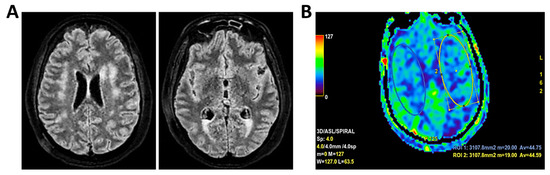

Figure 6.

MRI of patient 1 group 2. A 63-year-old man with a history of hypertension, dyslipidemia, and prior pulmonary lobectomy was admitted to the ER in a drowsy but verbally responsive state. His wife reported a recent episode of vomiting followed by loss of consciousness and tonic–clonic seizures. He was uncooperative and tremulous but afebrile, although a febrile episode had occurred in the preceding days. A lumbar puncture led to a diagnosis of Neisseria meningitidis type B meningitis. Ceftriaxone 2 g IV every 12 h was initiated. Brain CT, chest CT, and angio-CT of the epiaortic vessels showed no acute abnormalities. Due to clinical deterioration and a further seizure with hypotension, the patient was sedated, intubated, and experienced an episode of ventricular tachycardia during CT imaging, requiring IV Amiodarone. The patient was transferred to the ICU. On day 2, TCCD showed no significant flow abnormalities, with only mild asymmetry in PI (1.11 right, 1.4 left), without evidence of intracranial hypertension. (A) MRI exam with perfusion study reveal areas of altered signal intensity, hyperintense on 3D axial FLAIR sequence, (B) with diffusion restriction in axial DWI sequence, indicative of subacute inflammatory processes. These areas were scattered, the most significant is located along the subpial cortical surfaces of the left precentral and supramarginal gyri. Additionally, MRI exam demonstrates leveled material of likely inflammatory nature in both occipital horns of the lateral ventricles (A,B). (C) MRI perfusion with ASL sequence shows normal and symmetrical CBF values. Blue circles indicate the region of interest (ROI) used for quantitative CBF analysis.